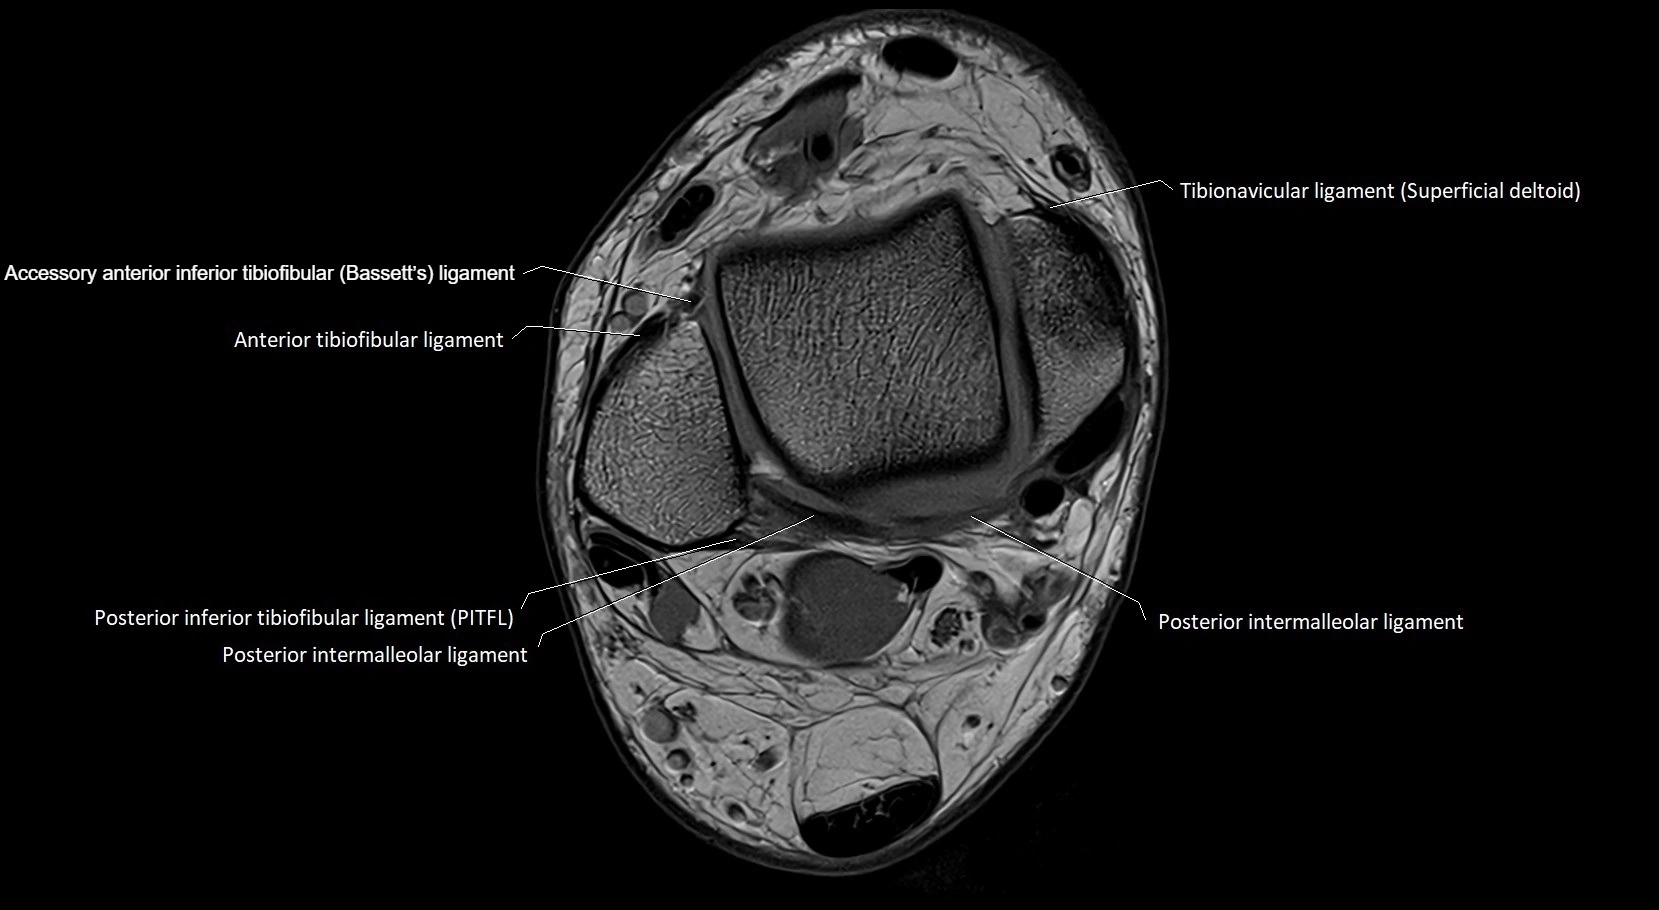

MRI image

image